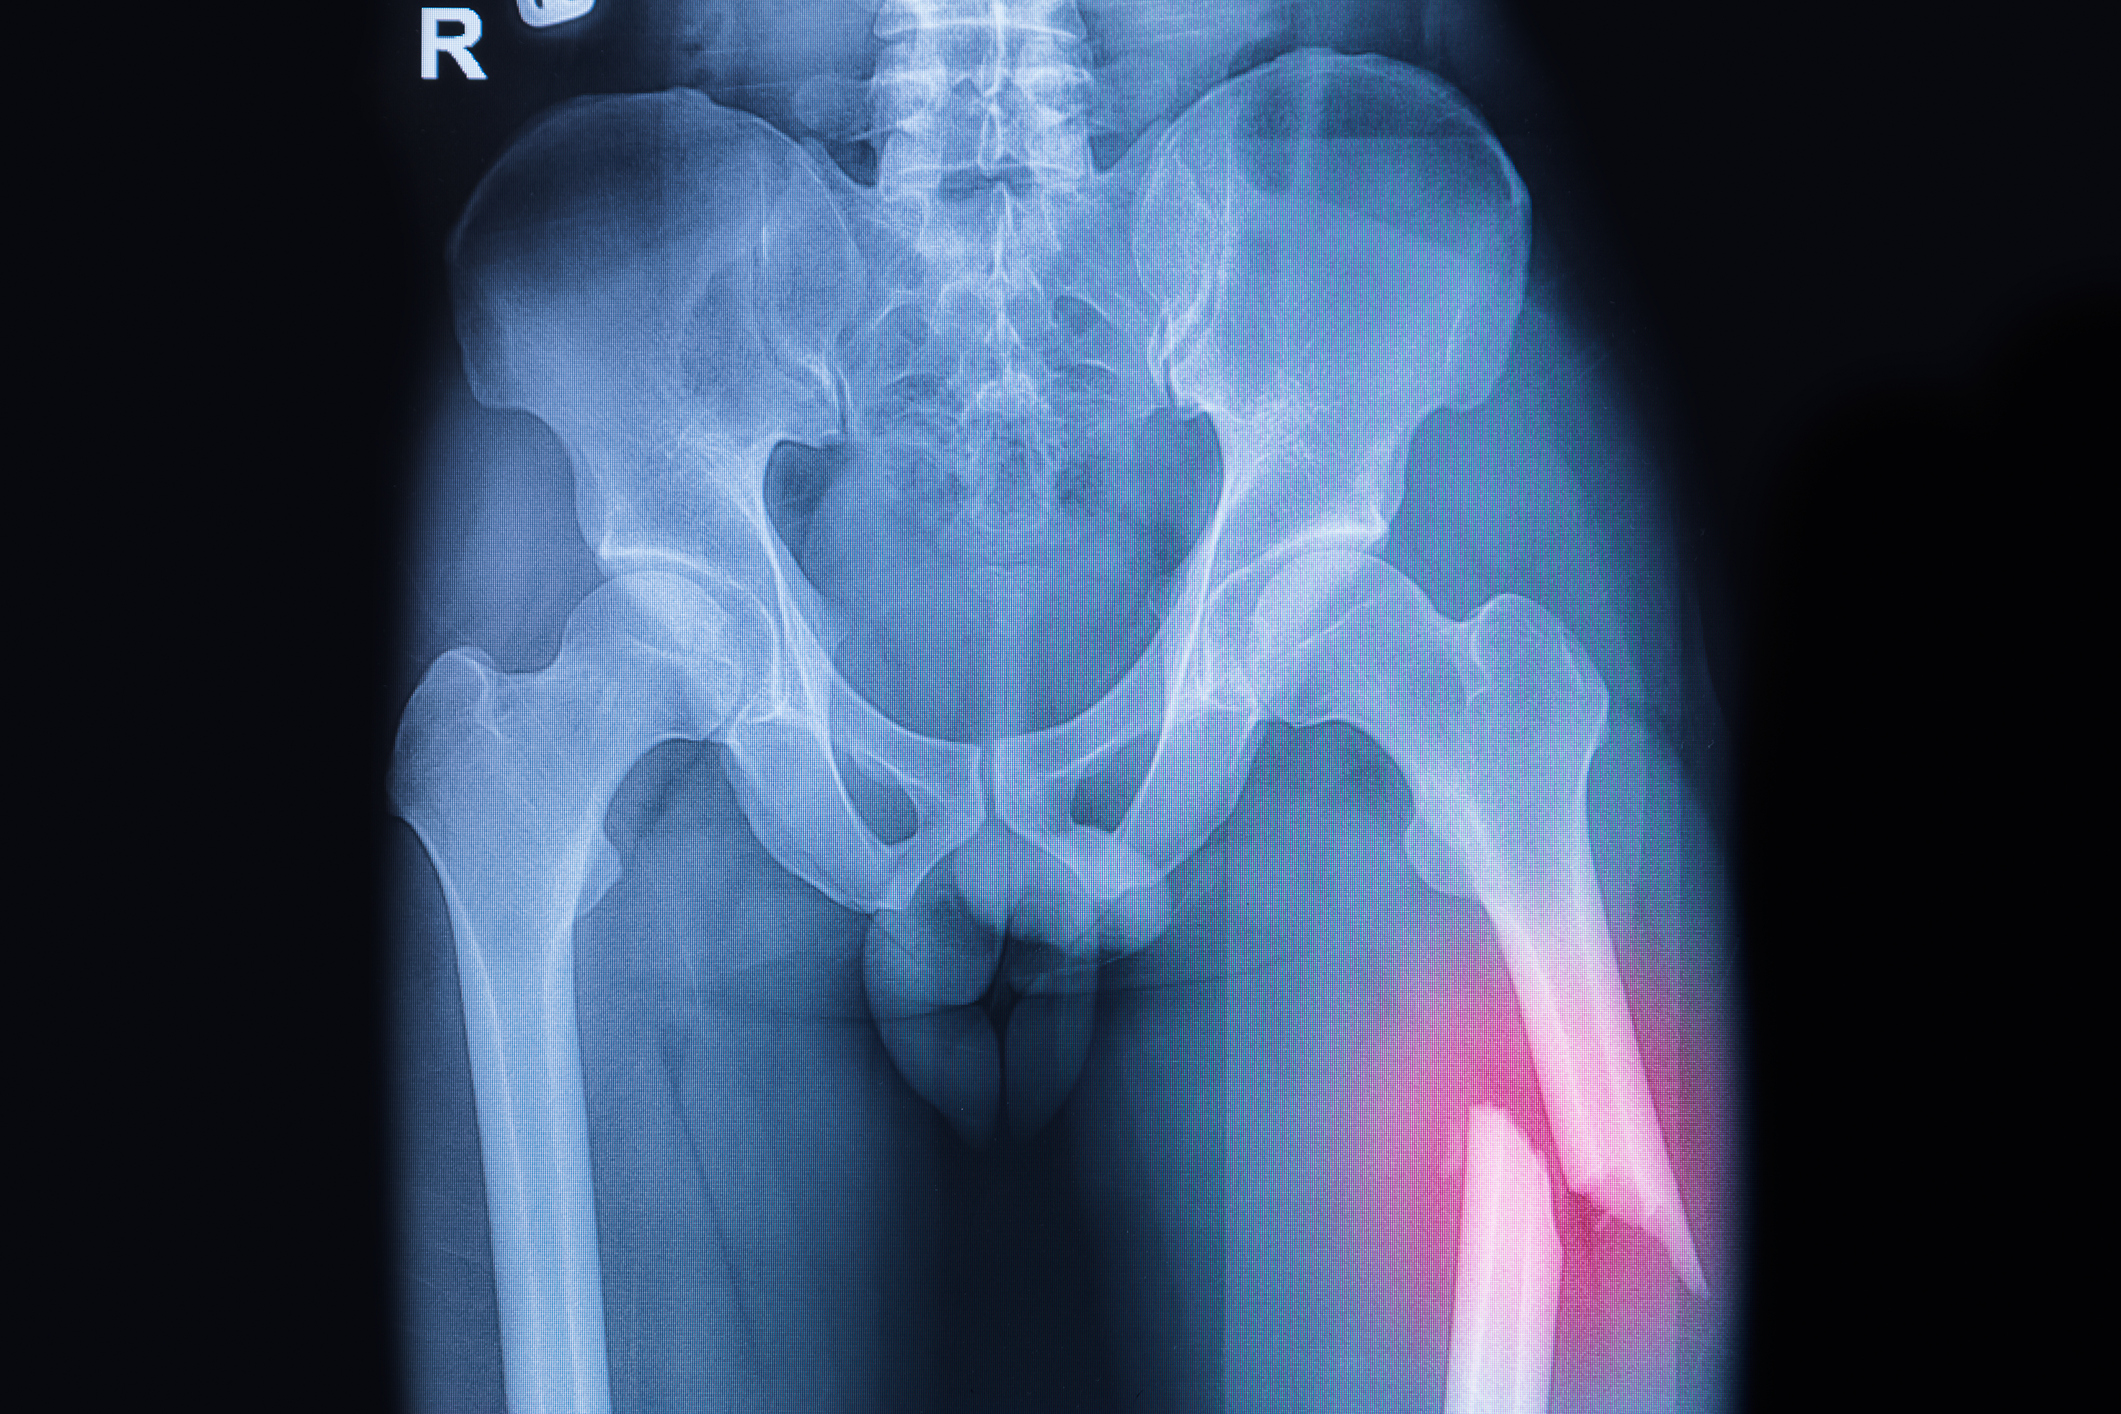

If you’re over the age of 50, then bone health is a serious concern—even more so if you’re a woman. When a person develops osteoporosis, their bones become weak and brittle, which increases the risk of fractures. Osteoporosis also negatively impacts mobility and can lead to isolation and depression. Osteoporosis is often called “the silent ...click here to read more